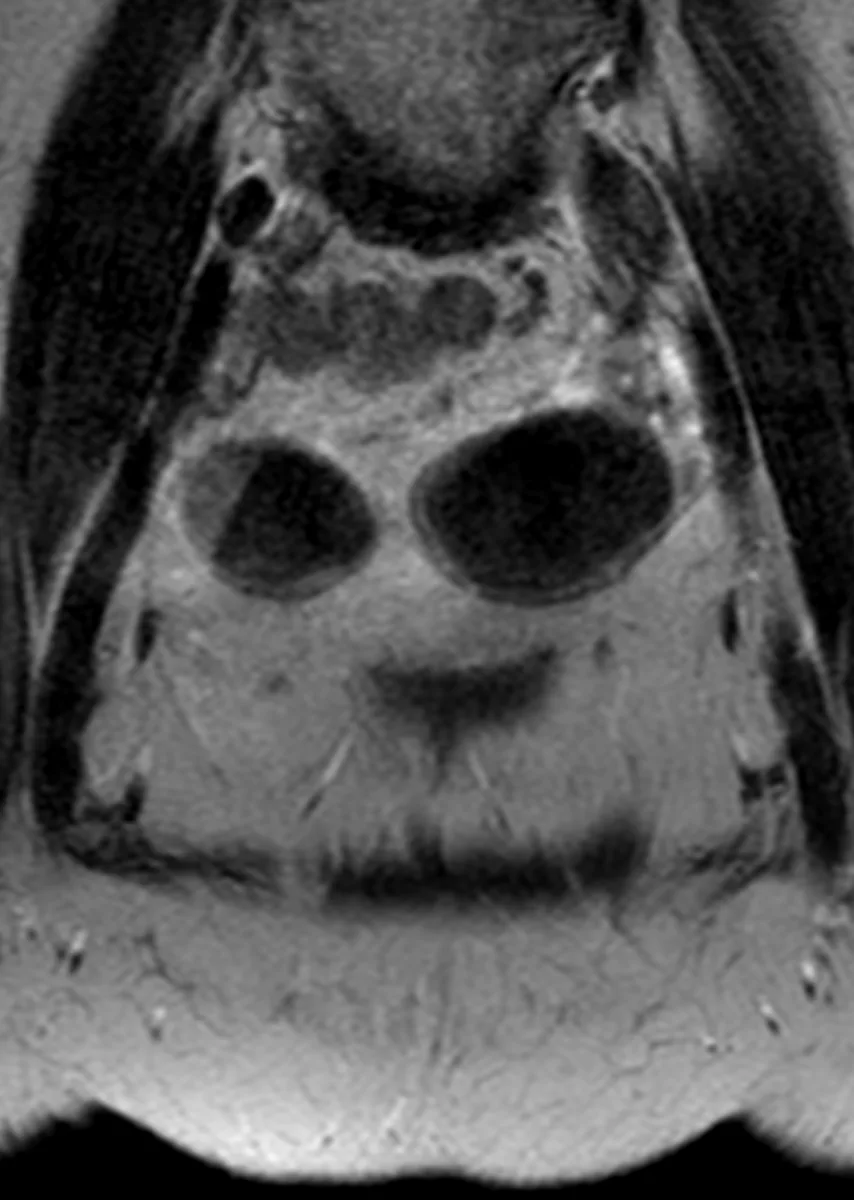

Обширная, ветвистая венозная мальформация (ранее известная, да и до сих пор тоже, как гемангиома) мягких тканей области коленного сустава.

Картина типичная, дифференциальная диагностика не требуется.

Представляет собой скопление аномальных, расширенных, извитых венозных сосудов, стенка которых гистологически не отличается от стенок обычных вен. Хорошо видны связи мальформации с обычными венами. Внутри некоторых из полостей видны выпадение сигнала, которые являются флеболитами (кальцинированными внутрисосудистыми тромбами).

Кстати, может никак не проявляться клинически, будучи даже таких больших размеров.